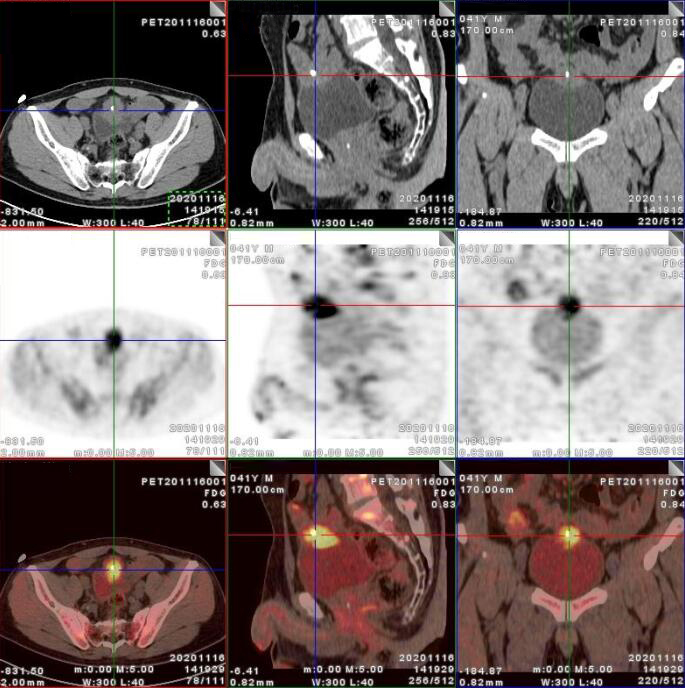

臍尿管擴(kuò)張,其管壁不均勻增厚,相應(yīng)區(qū)域膀胱頂前壁見一軟組織密度塊影,呈縱向生長,形態(tài)不規(guī)則,大小約3.3x3.8x6.3cm,內(nèi)見斑點(diǎn)鈣化!

膀胱頂前壁軟組織腫塊,放射性攝取SUV Max4.5

膀胱頂前壁軟組織腫塊,放射性攝取SUV Max4.5,延時(shí)4小時(shí)SUV Max8.3